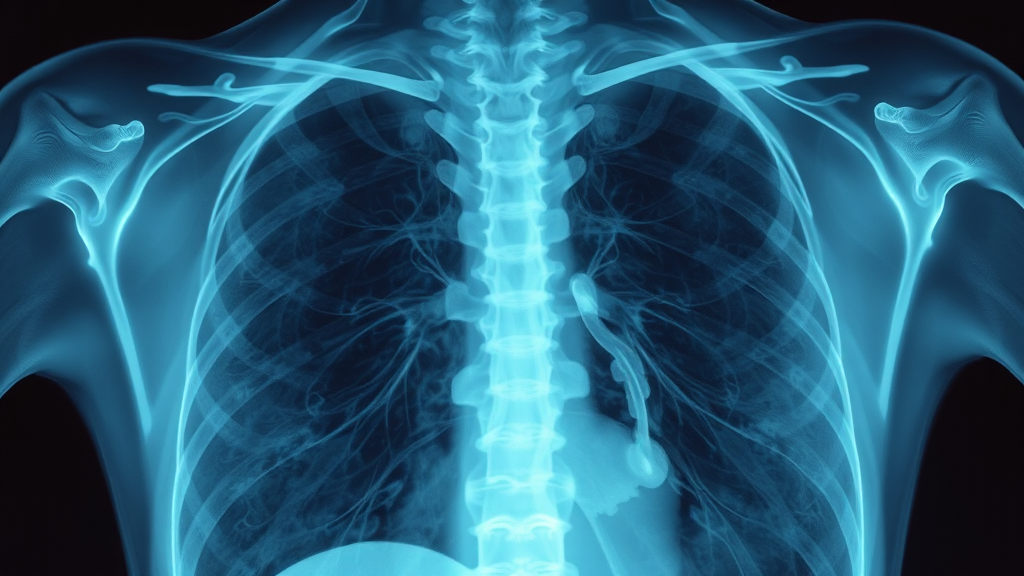

흉부 X-ray 검사

폐렴 진단은 흉부 X-ray 검사가 기본입니다. 흉부 X-ray를 통해 폐의 염증 부위를 확인하고, 폐렴의 정도를 파악할 수 있죠. 필요에 따라 혈액 검사를 통해 염증 수치를 확인하고, 객담 검사를 통해 원인균을 파악하기도 합니다. 객담 검사는 어떤 균이 폐렴을 일으켰는지 정확히 알아내, 그에 맞는 항생제를 선택하는 데 도움을 준답니다.

폐렴 치료와 더불어 중요한 건 정확한 진단입니다. 흉부 X-ray 검사는 폐렴 진단의 가장 기본적인 검사 방법이고요. 혈액 검사를 통해 염증 수치를 확인하고 감염 여부를 판단할 수 있어요. 가래 검사를 통해 원인균을 분석하고, 어떤 항생제가 효과적인지 결정하는 데 도움을 받을 수도 있고요. 폐렴은 초기에 발견해서 적절한 치료를 받는 것이 정말 중요해요. 만약 기침이 3일 이상 지속되거나 호흡곤란이 느껴진다면, 꼭 병원을 방문해서 진료를 받아보세요. 20대 초반의 한 환자분은 지속되는 고열로 동네 의원에서 감기약을 처방받았지만 호전되지 않아, 결국 종합병원에서 폐렴 진단을 받고 입원 치료를 받으셨다고 해요. 약 복용 후에도 증상이 나아지지 않는다면, 다른 병원을 방문하는 것도 좋은 방법이에요.

폐렴을 진단하는 가장 기본적인 방법은 무엇인가요?

흉부 X-ray 검사가 폐렴 진단의 가장 기본적인 방법입니다. 흉부 X-ray를 통해 폐의 염증 부위를 확인하고 폐렴의 정도를 파악할 수 있습니다.